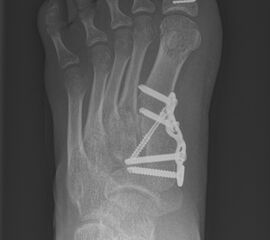

Wachstumslenkung mit moderner Klammer oder eight plate

Bei offenen Wachstumsfugen kann über eine Steuerung des Wachstums mit einer Klammer (Blount-Klammer/Flex Tack) oder kleinen Plättchen (Eight Plate) eine Korrektur von Achsabweichungen in der sagittalen und coronaren Ebene erreicht werden (Abb. 8). Der Hautschnitt beträgt ca. 1,5 - 2 cm und die so versorgten Kinder können ihre Extremität direkt postoperativ schmerzadaptiert voll belasten. Die wachstumslenkende Operation mit einer Klammer oder einem Plättchen besitzt ein enormes Korrekturpotential und erspart dem Kind oder Jugendlichen umfangreiche Umstellungsosteotomien und Plattenosteosynthesen, welche eine Schnittlänge von 15 cm und eine Entlastung des operierten Beines von 4-6 Wochen erforderlich machen.

Abb. 8 a-g: Genua vara prä- und postoperativ versorgt mit Flex Tacks (a-b) und ein Genu valgum versorgt mit Eight Plate an der medialen Femurkondyle (c); Spitzfuß bei congenitalem Klumpfuß und einem Flat Top Talus mit präoperativem Röntgenbild seitlich und der deutlich nach dorsal stehender Tibia(d); intraoperative Bilder der Epiphysiodese mittels Eight Plate zur Wachstumslenkung der distalen Tibia in die Extension (e-f) und postoperativer Verlauf nach sechs Monaten mit regelrecht stehender Tibia über dem Talus durch die distale Extension (g).